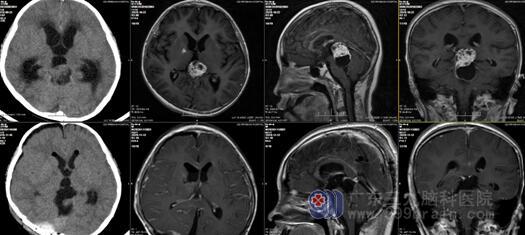

患者无头痛、恶心呕吐及肢体抽搐,一般状态良好。查体:神志清楚,对答切题,头部创口愈合良好,达1级/甲等愈合,双瞳孔等大同圆,直径3.0mm,对光反射灵敏,颈无抵抗,四肢肌力5级,肌张力正常,生理反射存在,病理征未引出。复查头颅MR提示肿瘤全切除。病理诊断:(松果体区)成熟型囊性畸胎瘤。

术前及术后MR对比,提示病变全切除。